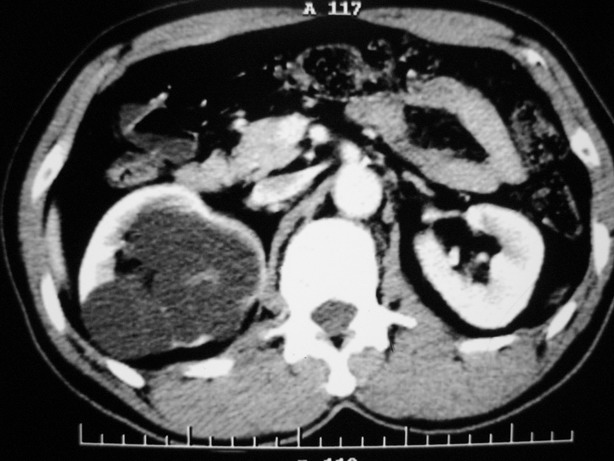

标题: CT10772:男性,48,右肾盂旁多囊性占位!

男性,48,体检发现,平时无症状。

平扫: